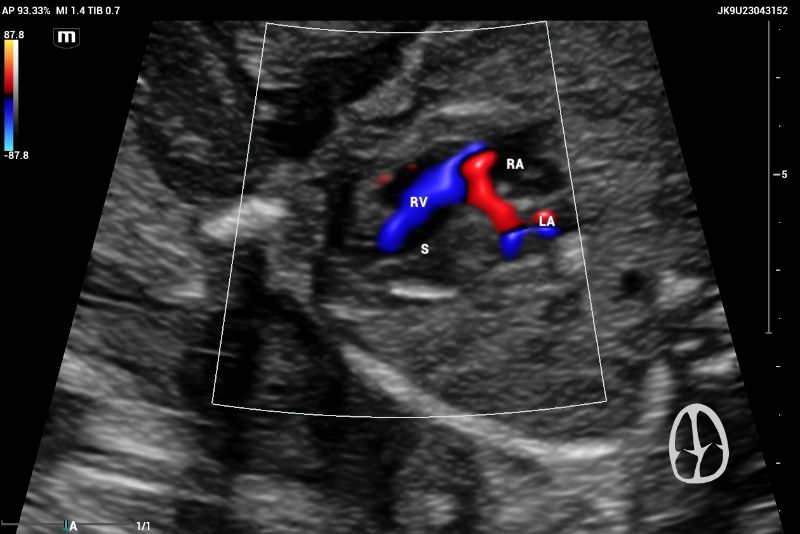

Example of normal echocardiography performed on Mindray Resona I9 system. Artery – ventricle concordance outflow tract showing pulmonary artery (PA) emerging of the right ventricle (RV)

Figure 4. Example of normal echocardiography performed on Mindray Resona I9 system. Artery – ventricle concordance outflow tract showing pulmonary artery (PA) emerging of the right ventricle (RV)